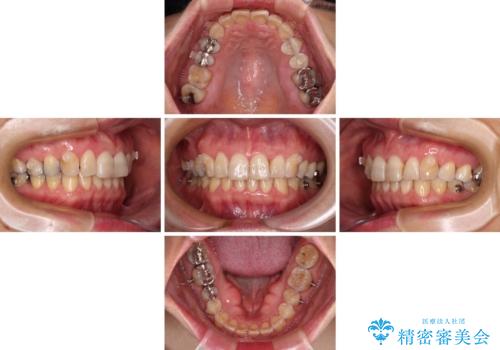

- 前歯のデコボコと上下正中のずれを気にして来院された患者様です。

下顎骨が骨格的にずれがあったため、しっかりと正中を合わせるとなるとワイヤー矯正が必要でしたが、マウスピース矯正を希望されたため、極力正中を合わせることを目標に、インビザラインにて矯正治療を行うこととしました。

インビザラインは、ワイヤー矯正と異なり、患者様がしっかりと使うということが治療成功の絶対必須条件となります。

十分な装着時間が達成できず、治療途中で後戻りを起こすことがあり、インビザラインの有効期限内に終了させることができませんでした。

ワイヤー矯正や別システムのマウスピース矯正を利用することで、何とか終了させることができました。